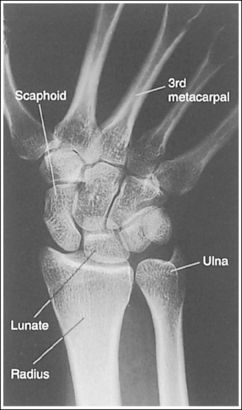

See Figure 4-29 and Box 4-11.

Contrast and density are adequate to demonstrate the scaphoid fat stripe.

• Significance of the scaphoid fat stripe. The scaphoid fat stripe is one of the soft tissue structures that should be visible on all PA wrist projections (Figure 4-30). It is convex and located just lateral to the scaphoid in an uninjured wrist. A change in the convexity of this stripe may indicate to the reviewer the presence of joint effusion or of a radial side fracture of the scaphoid, radial styloid process, or proximal first metacarpal.

The wrist is positioned in a PA projection. The radial and ulnar styloids are at the extreme lateral and medial edges, respectively, of each bone. The radioulnar articulation is open, and superimposition of the metacarpal bases is limited.

• Rotation of the wrist and forearm is controlled by the position of the hand, elbow, and humerus. A PA projection is accomplished by abducting the humerus until it is positioned parallel with the IR and the elbow is in a lateral projection. The hand is then pronated, placing the wrist in a PA projection (Figure 4-31).